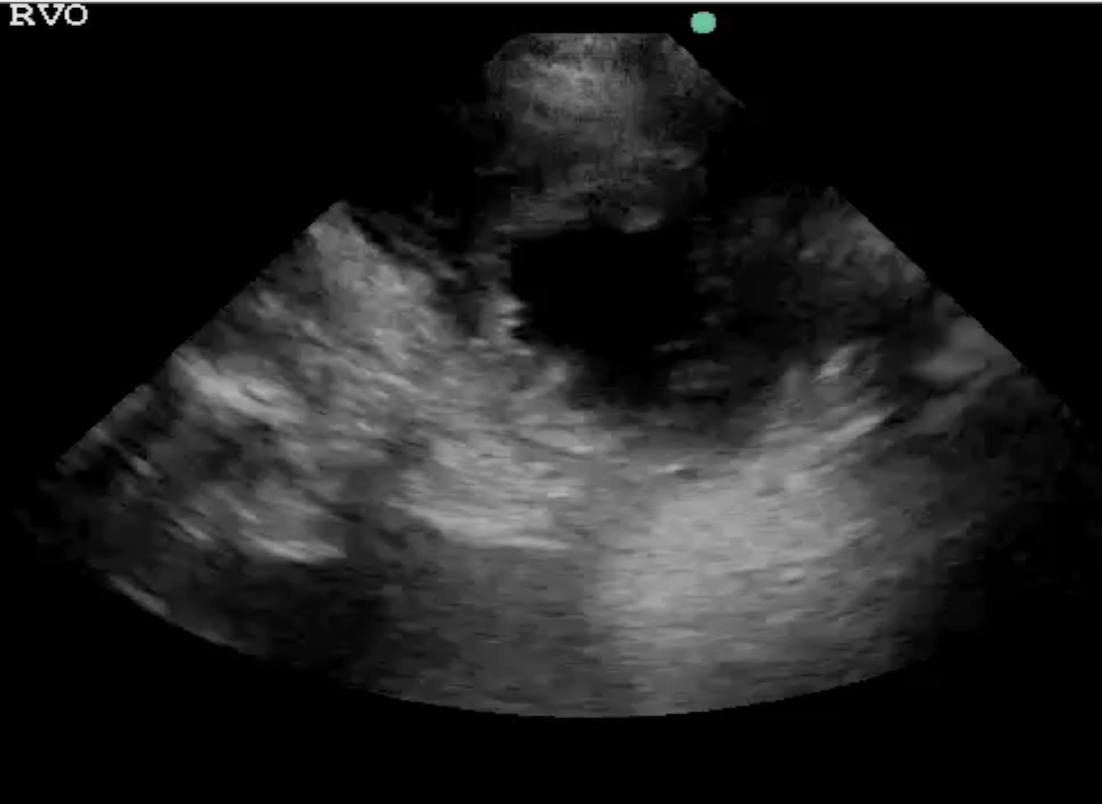

• Lung ultrasound

• Lung ultrasound interpretation for pulmonary congestion and fluid tolerance

• Lung ultrasound for pulmonary edema, pneumonia, and pleural effusions